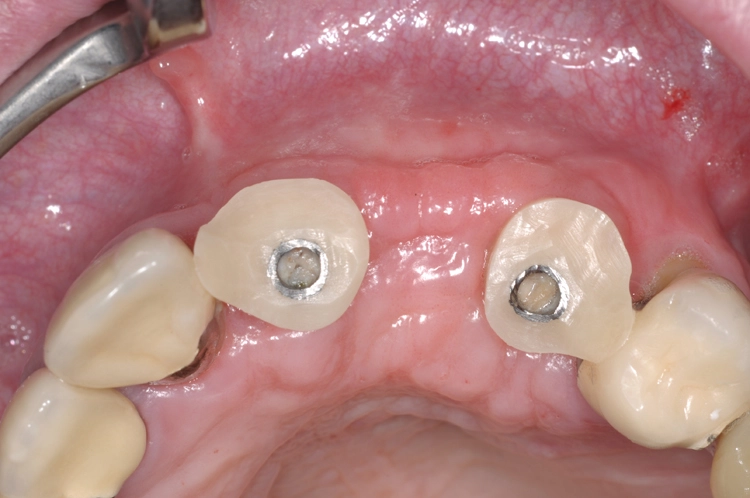

Nach einer viermonatigen Einheilphase erfolgte die Implantation von zwei Straumann® BLT Implantaten mit einer Länge von 12 mm und einem Durchmesser von 4,1 mm im Bereich des aufgebauten Knochens (Ausgangssituation siehe Abb. 8). Vor der Implantation fand vorbereitend eine Glättung der Oberfl äche statt, um scharfe Kanten zu beseitigen (Abb. 9). Für die korrekte prothetische Positionierung der Implantate kamen individuell gefertigte Orientierungsschablonen zum Einsatz, anschließend wurden die Implantate für eine verschraubte Brücke gesetzt (Abb. 10).

Praxis Dr. Robert Würdinger